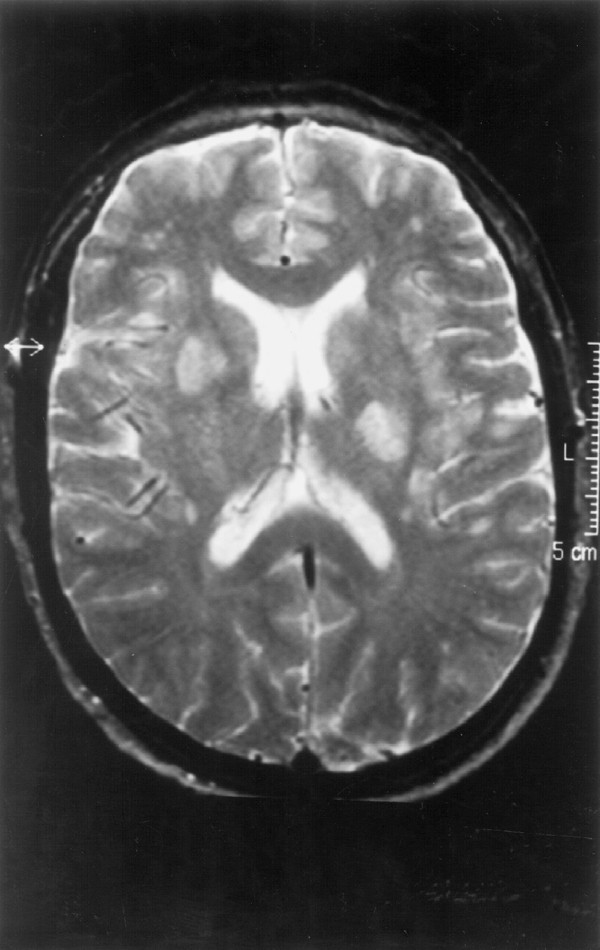

A 48-year-old man was diagnosed of Ph+, bcr/abl/ CML in the first chronic phase in April 1998. After therapy with hydroxyurea, an allogeneic transplantation was carried out in October 1998 using his HLA-identical sister's G-CSF-mobilised PBPC after CD34/ positive selection. Conditioning included high-dose cyclophosphamide and fractionated total body irradiation, and CsA (300 mg/day) was given for GVHD prophylaxis. Streptococcus sanguis sepsis developed on day +9 and was successfully treated with piperazilin-tazobactam. Platelet (>25×109/l) and neutrophil (>0.5×109/l) recovery were documented, respectively, on days /11 and /15. Neither symptoms nor signs of GVHD were noted during the post-transplant period. On day +37 fever reappeared; blood and urine cultures were negative and amphotericin was started. A thoraco-abdominal CT scan, a hepatosplenic ultrasound exam and a CT scan of the paranasal sinuses were normal. The creatinine plasma levels increased up to 261 μmol/l prompting discontinuation of amphotericine; CsA was tapered and ultimately discontinued on day +54, leading to a rapid and definitive normalisation of renal function by day +57. Hypertension developed and was sequentially treated with nifedipine, captopril and IV labetolol without adequate control. On day +57, speech tremor and weakness were noted; the sodium level was normal (139 mmol/l). On day +60, diplopia appeared; a cranial CT scan was normal and the CSF was acellular with a normal glucose and protein content; serum sodium levels were normal (137 mmol/l). On day +64 the fever disappeared but bradipsychia developed, the conscience level diminished, and dysarthria and left supranuclear facial paresis were evident; hyponatremia (123 mmol/l) with normal renal function was recorded. That day, an MRI examination (Figures 1 and 2) disclosed multiple lesions in the basal ganglia on both sides, in the right putamen, the left globus pallidus and right subthalamic region extending to the mesencephalic peduncles, pons and middle cerebellar left peduncle; lesions were also seen in the subcortical and deep white matter bifrontal lobes and the left external capsule presenting as high-intensity areas in T2-weighted images, with moderate low intensity in T1-weighted images, and without mass effect; all these multiple supra-infratentorial lesions strongly suggested CEPM. The patient's condition worsened on day +65, with dysphagia, tachypnea and increased respiratory effort with normal O2 saturation; this picture, attributed to pseudobulbar palsy, prompted the initiation of mechanical ventilation for 4 days. After extubation the patient continued afebrile, his blood pressure was normal, and the neurological signs and symptoms gradually disappeared. A repeat MRI on day +84 was normal. Blood counts at discharge on day +88 showed Hb 9.6 g/dl, WBC 4.0×109/l (55% segmented neutrophils, 8% eosinophils, 1% basophils, 28% lymphocytes and 8% monocytes), platelets 88×109/l, and normal sodium and creatinine levels. CsA was not reintroduced. The patient remains free of symptoms attributable to CEPM and in molecular remission of CML 28 months after allogeneic haematopoietic transplantation. Figure 3 displays a time-course chart with the main clinical and laboratory features of this case.